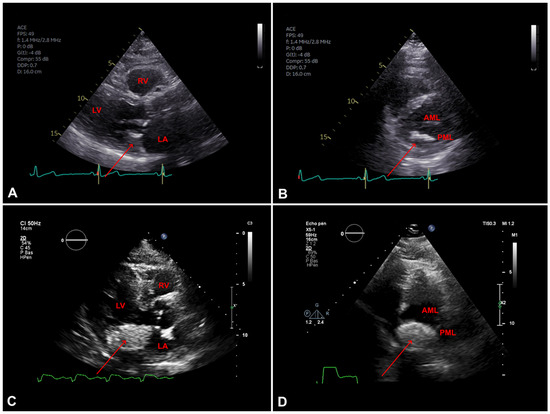

Myocardial infarction with nonobstructive coronary arteries (MINOCA): Myocardial infarction (MI) with non-obstructive coronary arteries (MINOCA) is defined as MI according to the fourth universal definition of MI [1] without coronary stenosis ≥50% on...